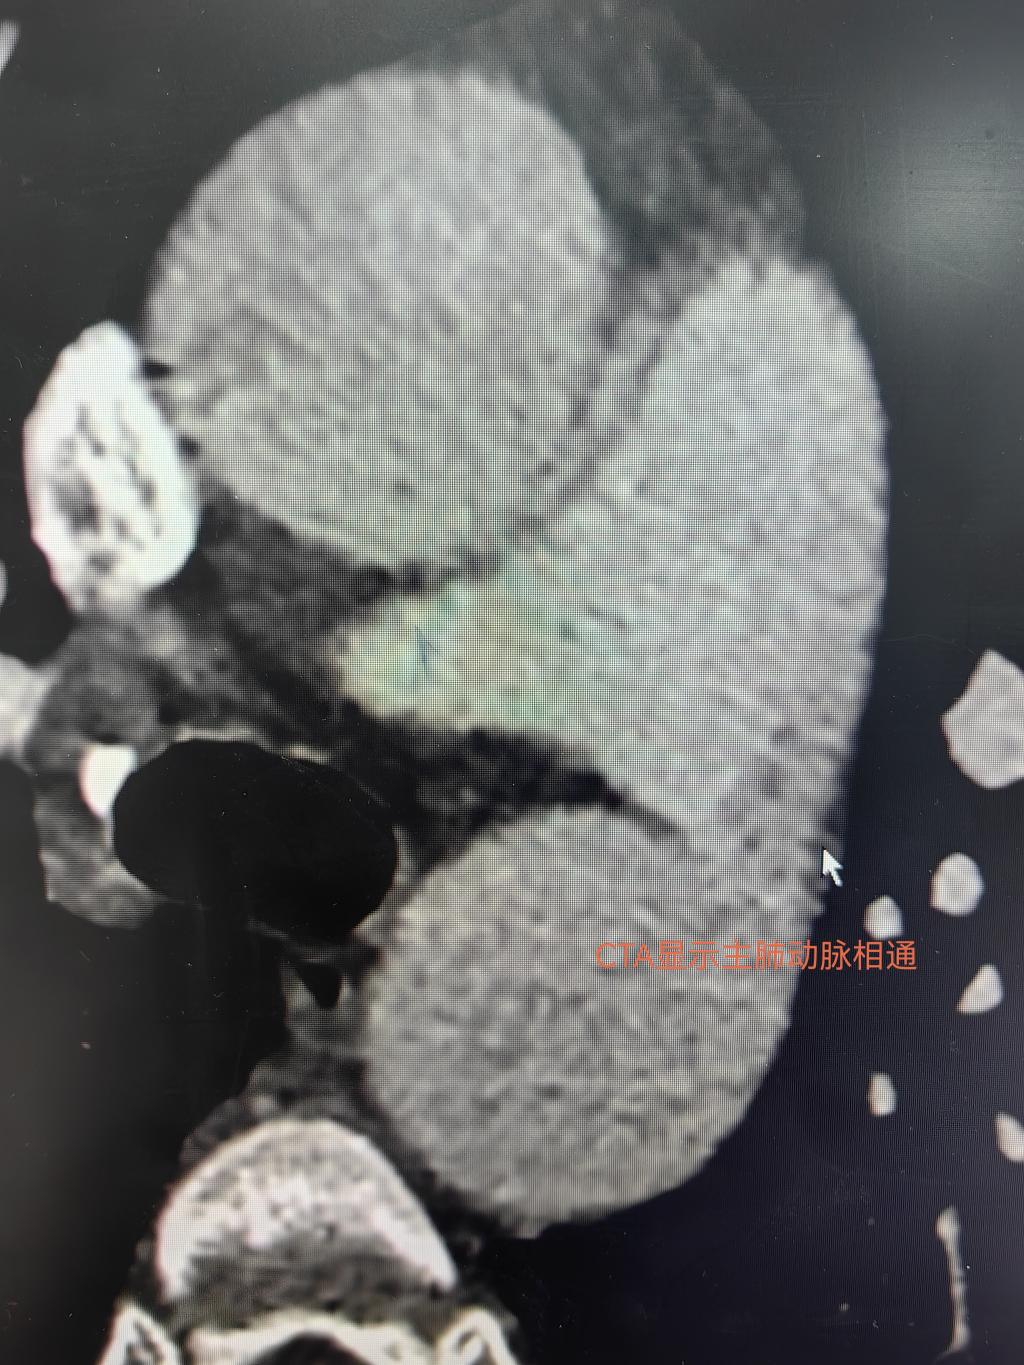

根据当地医院初步的心脏超声结果及入院查体发现,患者很快就被诊断为动脉导管未闭(PatentDuctusArteriosus,PDA),这是一种并不复杂的先天性心脏病,在专业的心脏外科也是相对容易治疗一类病变。但当患者进行术前检查时,专长心脏诊断的超声科金鑫医生却惊诧的发现患者的PDA畸形远比估计的复杂和严重,一方面,根据超声测量PDA的内径可粗达15.9mm,属于极其罕见的巨大型PDA;另一方面,患者还同时合并卵圆孔未闭,经胸超声即可看到明显的房水平右向左分流,因而患者属于复合型的先天性心脏病。为了准确评估病变程度,进一步为患者安排了肺动脉血管成像,影像科邓蕾医生仔细进行了主动脉及肺动脉不同节段水平的精确测量,证实了巨大PDA的存在(图1、2)。诊断明确后,心血管外科在裴斐主任主持下对患者手术方案进行讨论,对由于患者的PDA过于粗大,现有常用的动脉导管未闭封堵器材难以适用,介入手术存在“巧妇难为无米之炊”的局面;全麻体外循环下开胸结扎动脉导管并缝合卵圆孔的手术成为必要的选择。但患者及家属由于家中有亲人因心脏病去世,谈及心脏停跳后进行手术完全心理排斥不愿接受。如果心脏不停跳单纯小切口结扎动脉导管,除了大血管解剖暴露差出血风险高,而且患者今后还需要再次介入手术处理卵圆孔未闭。进退维谷之际,相里伟医生一边不厌其烦和患者家属反复解释病情,告知其疾病的影响和手术的必要性,另一边通过医院设备科主动联系生产介入封堵器材的企业,预定调拨大规格非常规的动脉导管未闭封堵器准备尝试微创治疗。与患者家属反复沟通后获得知情同意后,最终确定了优先方案为局麻下尝试经皮动脉导管未闭封堵术,根据封堵后情况再决定是否行卵圆孔未闭治疗的手术方案,备选方案为全麻下外科动脉导管未闭结扎术。